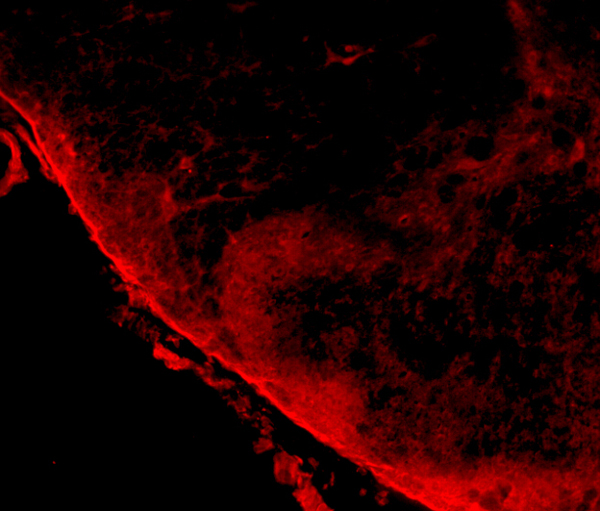

IHC (Immunohistochemistry)

(AAA327178 at 1/100 staining Human liver cancer tissue by IHC-P. The sample was formaldehyde fixed and a heat mediated antigen retrieval step in citrate buffer was performed. The sample was then blocked and incubated with the antibody for 1.5 hours at 22 degree C. An HRP conjugated goat anti-rabbit antibody was used as the secondary.)